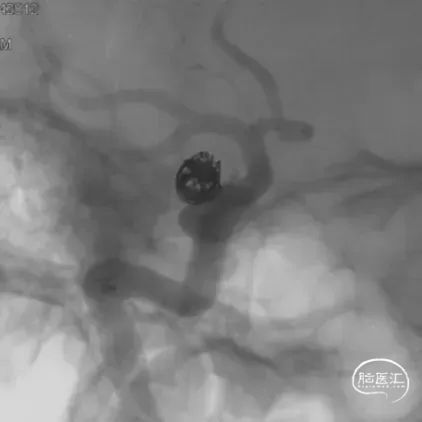

右侧颈内动脉眼动脉段-海绵窦段串联两枚动脉瘤,分别大小约:

① 8.8mm*5.9mm*5.2mm,瘤颈宽7.0mm;

② 6.8mm*4.3mm*3.6mm,瘤颈宽3.3mm。

支架导管及弹簧圈微导管先后超选到位,其中弹簧圈微导管超选入远端眼动脉段动脉瘤内备用,根据测量结果,选用YonFlow®血流导向密网支架 4.5mm/30mm、弹簧圈9mm/40cm,先部分推出弹簧圈在动脉瘤内提供保护。再释放密网支架。